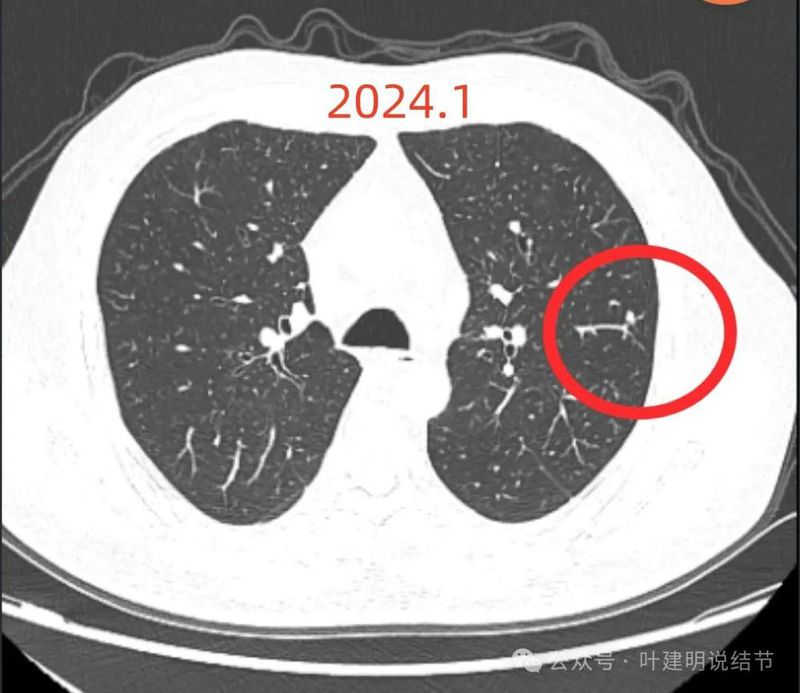

2024年1月病灶较3个月前明显增大进展,是实性小结节,有微小血管走向病灶。

2024年5月病灶又有增大进展,实性密度,轮廓较清。